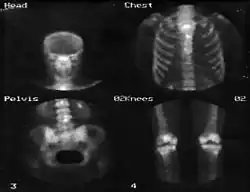

Também é possível obter uma sequência de imagens dinâmicas e sincronizá-las com outros sinais como, por exemplo, um eletrocardiograma, de forma a gerar imagens do coração durante a sístole e a diástole.[3] A figura 5 apresenta um exemplo de imagem obtida por uma câmara gama.